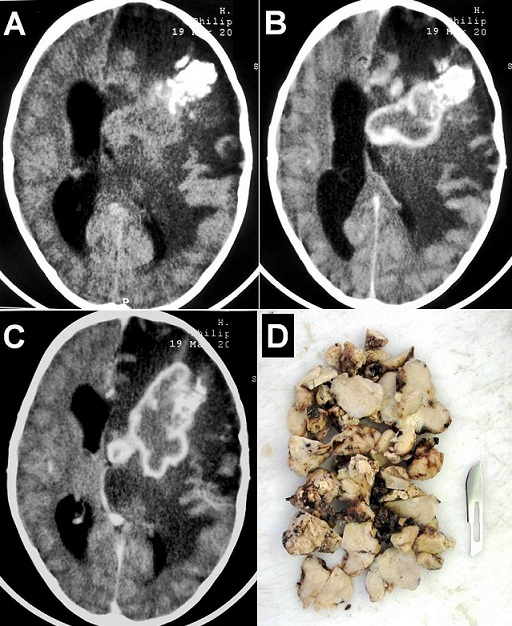

A 6-year-old boy, with no past medical history, presented with progressive headache, vomiting, right side weakness since 3 months without fever or seizures. On examination, he was conscious with a stiff neck and right hemiplegia. Brain computed tomography-scan showed a heterogeneous calcified large mass-like lesion in the left fronto-temporo-parietal region, irregular contrast enhancement and extensive perilesional edema with important mass effect (A-C). There was a strong suspicion of malignant tumor. Routine blood tests and chest X-ray were normal. Magnetic resonance imaging was requested but not made because of the rapid deterioration of the state of consciousness of the child. The patient was operated urgently. At operation there was a large intra-axial yellowish, firm, and relatively avascular lesion. Total excision of the mass was done (D). Histological features were consistent with tuberculoma. Serological test for HIV was negative. The patient improved progressively and was discharged on antituberculous treatment with a good outcome. Intracranial tuberculoma should always be considered in the differential diagnosis of solitary and large focal brain lesions, particularly in patients of tuberculosis endemic areas. In our patient, surgical excision not only helped to establish the histological diagnosis but also helped to resolve the compressive symptoms.